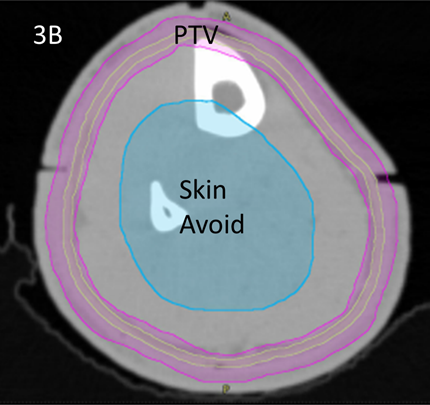

Wires were placed over all RO marks to capture these positions on the CT scan. The latter was done at 2mm increments. Bi-valved 3DPB was then ordered and was fitted at a second simulation session. The RO then contoured the clinical target volume (CTV) and planning target volume (PTV)8 according to the national protocol7 using MIM MaestroTM planning software. A contour volume called “Skin Avoid” was created by having a structure that extended on all the slices on which there was a PTV. This volume was made by the RO and was 1.5cm inside the PTV into the centre of the leg. The Skin Avoid structure was prescribed to receive a dose less than a mean of 25 Gy. See Figure 3.

Figure 3B The RO also contours the PTV, in magenta, according to the national protocol7 using MIM MaestroTM planning software. The PTV was prescribed 45Gy in 25 fractions. A volume called “skin avoid” was created by having a structure, here in cyan, that extends on all the slices on which there is a PTV. It is made by being inside and 1.5cm from the PTV into the centre of the leg. The Skin Avoid structure was prescribed to receive a dose less than a mean of 25 Gy.